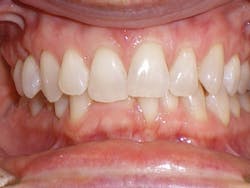

Compare the inclination of the long axis of teeth on #12 before and after treatment.

Figure 3

Sandra is a common example of a patient having a malocclusion that is the direct cause of her recession, and abfractions. When we first examined Sandra, her chief complaint was her smile (see Figure 3). She was unhappy with her smile and "crooked" teeth and had the desire to fix them.

Sandra expressed to us that she looked into clear aligner therapy but was told she was not a candidate. She was told she would need two years in braces and possibly some teeth extracted. These treatment options were undesirable, so she chose to do nothing. We assured her that she was an excellent candidate for clear aligner therapy, and her treatment time would be 14 months with no extractions.

At the consultation, Sandra's photos were used to teach. The photo of the lower crowding with the lingual plaque and calculus was used to teach Sandra the difference between crowded teeth and aligned teeth. We also informed her that her teeth are not actually "crooked" (her chief complaint). The mandibular occlusal view pointed out her V-shaped arch provided no room for her teeth to fit within the arch.

The remaining photos were used to teach the difference between a good bite and a bad bite. Sandra learned about clefting, recession, abfractions, and the visible areas of enamel wear on multiple teeth. Sandra understood that clear aligner therapy would change her bad bite to a good bite, resulting in a beautiful, healthy smile. My goal went further than that. I knew the benefits of aligned teeth include increased longevity, a healthy periodontium, and proper occlusion for her to enjoy a lifetime of oral health.

Sandra was excited to begin treatment. So her case was submitted, developed, and delivered in short order. Her treatment involved 24 aligners, which took exactly 12 months of treatment time.

Upon completion of treatment, she had a healthy, stable, and functional occlusion. Notice the clefting, recession, and abfraction improvements in the photographs related to her case. This validates my objection to the current standard of care of "waiting and watching" for conditions to worsen. Instead, my hygienists and I educate patients on the long-term solutions of clear aligner therapy so they can make educated choices regarding their oral health.